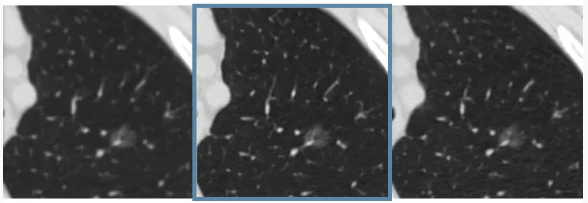

YJCT是基于深度学习技术研发的人工智能重建增强成像软件,旨在为医院和第三方影像中心提供针对高质量CT的图像增强解决方案。通过图像重建增强技术,YjCT可显著提升CT影像数据的空间分辨率,并降低图像噪声与电离辐射,提升患者检查的安全。目前软件已进入商品化阶段,以期让更多患者受益。